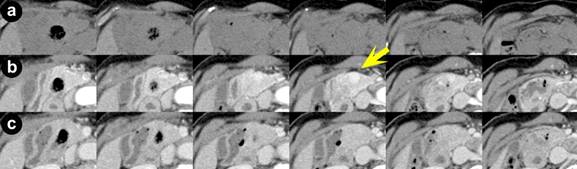

A seventy-five-year-old woman who experienced an episode of unconsciousness due to hypoglycemia with a serum glucose level 34 mg/dL was referred. Laboratory findings were within normal limits except for a fasting serum glucose level of 48 mg/dL. IRI, CPR, and other hormone levels were within normal limits. Anti-insulin antibody was negative. Routine abdominal CT scan showed no remarkable findings. ASVS was performed which suggested a tumor in the head/body of the pancreas. Early-phase thin-slice CT showed a distinct well-enhanced 9 mm tumor in the head of the pancreas during the arterial phase at 45 seconds (timing individualized for this patient) after the administration of contrast definitively only on one slice (Figure 2, yellow arrow). A tumor in the head of the pancreas was palpable intraoperatively and IOUS demonstrated a low echoic mass in the same area. Enucleation of the 12 mm tumor was performed and the tumor was diagnosed as an insulinoma, grade G1 with an MIB-1 index <1%. Immunohistochemistry showed synaptophysin (+), insulin (+), glucagon (-), somatostatin (-), and pancreatic polypeptide (-). She was discharged from the hospital uneventfully and has had no recurrence 61 months after operation.

Figure 2. Axial CT scan of Patient #2 (slice thickness: 3 mm) at 0 seconds (pre-contrast) (a.), 45 seconds (b.), and 80 seconds (c.) after the administration of contrast agent, respectively. Only in one slice of the 45 second scan, a 9 mm high density lesion in the pancreatic head is demonstrated (indicated by a yellow arrow), whereas the same slice in the 80-second scan shows no abnormality. |